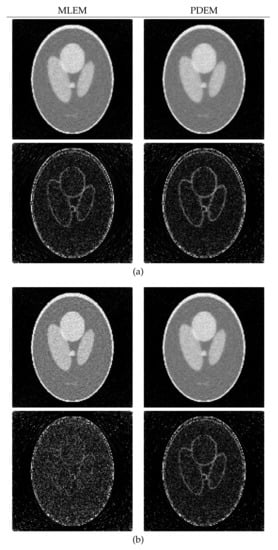

4.1. Reconstruction Using Numerical Phantom

4.2. Reconstruction Using Physical Phantom